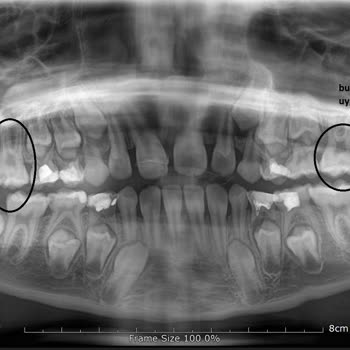

25.12.2023 tarihinde Ağız ve Diş sağlığı hastanesine eşimi götürdüm 4 tane gömülü 20 lik diş i vardı ve götürmeden önce çok ağrı yapıyordu. Sabah 9 da gittiğimizde akşama kadar cerrahın boş vakti yok dendi beklerseniz saat 16.30 te sizi alacak dendi. Bizde akşama kadar bekledik sonra kaydımızı açtır...

Hospident Fatih şubesinde 2 yılı aşkındır pedodontist d. Ml. İle dişlerimizin kontrol altına olduğunu düşünürken aslında pek de öyle olmadığını anladık. Şöyle ki, 8 yaşındaki çocuğunuzun kalıcı dişlerini korumak adına fissür işlemi yaptırmak için doktorunuz planlama yapıyor. Size başka işlemlerle il...